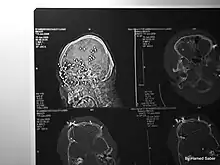

Kinetic-impact-projectiles (KIPs) also known as baton rounds, or rubber/plastic bullets are non-lethal projectiles used for crowd control purposes by riot police.[6][7][8] KIPs are marketed as non or less-lethal weapons used for the purposes of dispersing crowds without causing penetrating wounds.[6] However, when used inappropriately and fired indiscriminately, they have been known to cause injuries leading to life-long disability, or even death.[6][7][9] Examples of KIPs include rubber or plastic bullets, bean bag rounds, sponge rounds (rounds with a softer nose/tip to limit impact) or pellet rounds of birdshot or buckshot.[6][7] Hosein Jafari, 28 at the time, was attending a protest in Tehran with Farzi when he was shot in the back of the head with a pellet gun.[10] Medical imaging scans shared on his Instagram page show 6 of the 8 pellets that entered his body remain, one in his neck and the rest in his head.[10] Abolfazl Adinezadeh, a 17 year old boy that had joined the Woman, Life, Freedom protests is one of many examples of protesters in Iran who have been killed as a result of close range discharge of KIPs.[9][11] Cases have also been reported in which protesters have either been killed, or lost an eye as a result of being hit directly by tear gas canisters.[7][12][13][14] Abolfazl Amirataie, a 16 year old boy who had joined protests on 22 September 2022 was shot directly in the head at close range with a tear gas canister, causing catastrophic damage to one side of his skull and brain.[15] After 8 months in a vegetative state, Amirataie succumbed to his injuries on 27 May 2023.[15]